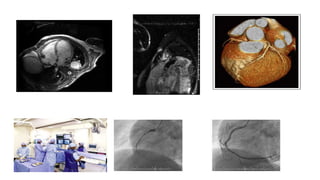

2e Cas clinique •Homme de 25 ans • Vu en consultation de pneumologie pour une dyspnée en aggravation. • Radiographie du thorax: Aspect de Pneumopathie interstitielle diffuse. Pas d'épanchement pleural démontré. Cœur globuleux => Prise en charge en pneumologie Devant l’absence d’amélioration: réalisation d’une échocardiographie et d’un dosage de Nt-proBNP

2e Cas clinique •Dosage de Nt-proBNP: 2024pg/mL ➢ Echocardiographie: ➢ Explorations complémentaires Coronaro, sérologies, biopsies, … négatives. ➢ IRM: Myocardite VG dilaté hypokinésie diffuse sévère, FEVG 25%. E/E'>15. Pas d'HTAP. VD dilaté. VCI congestive.